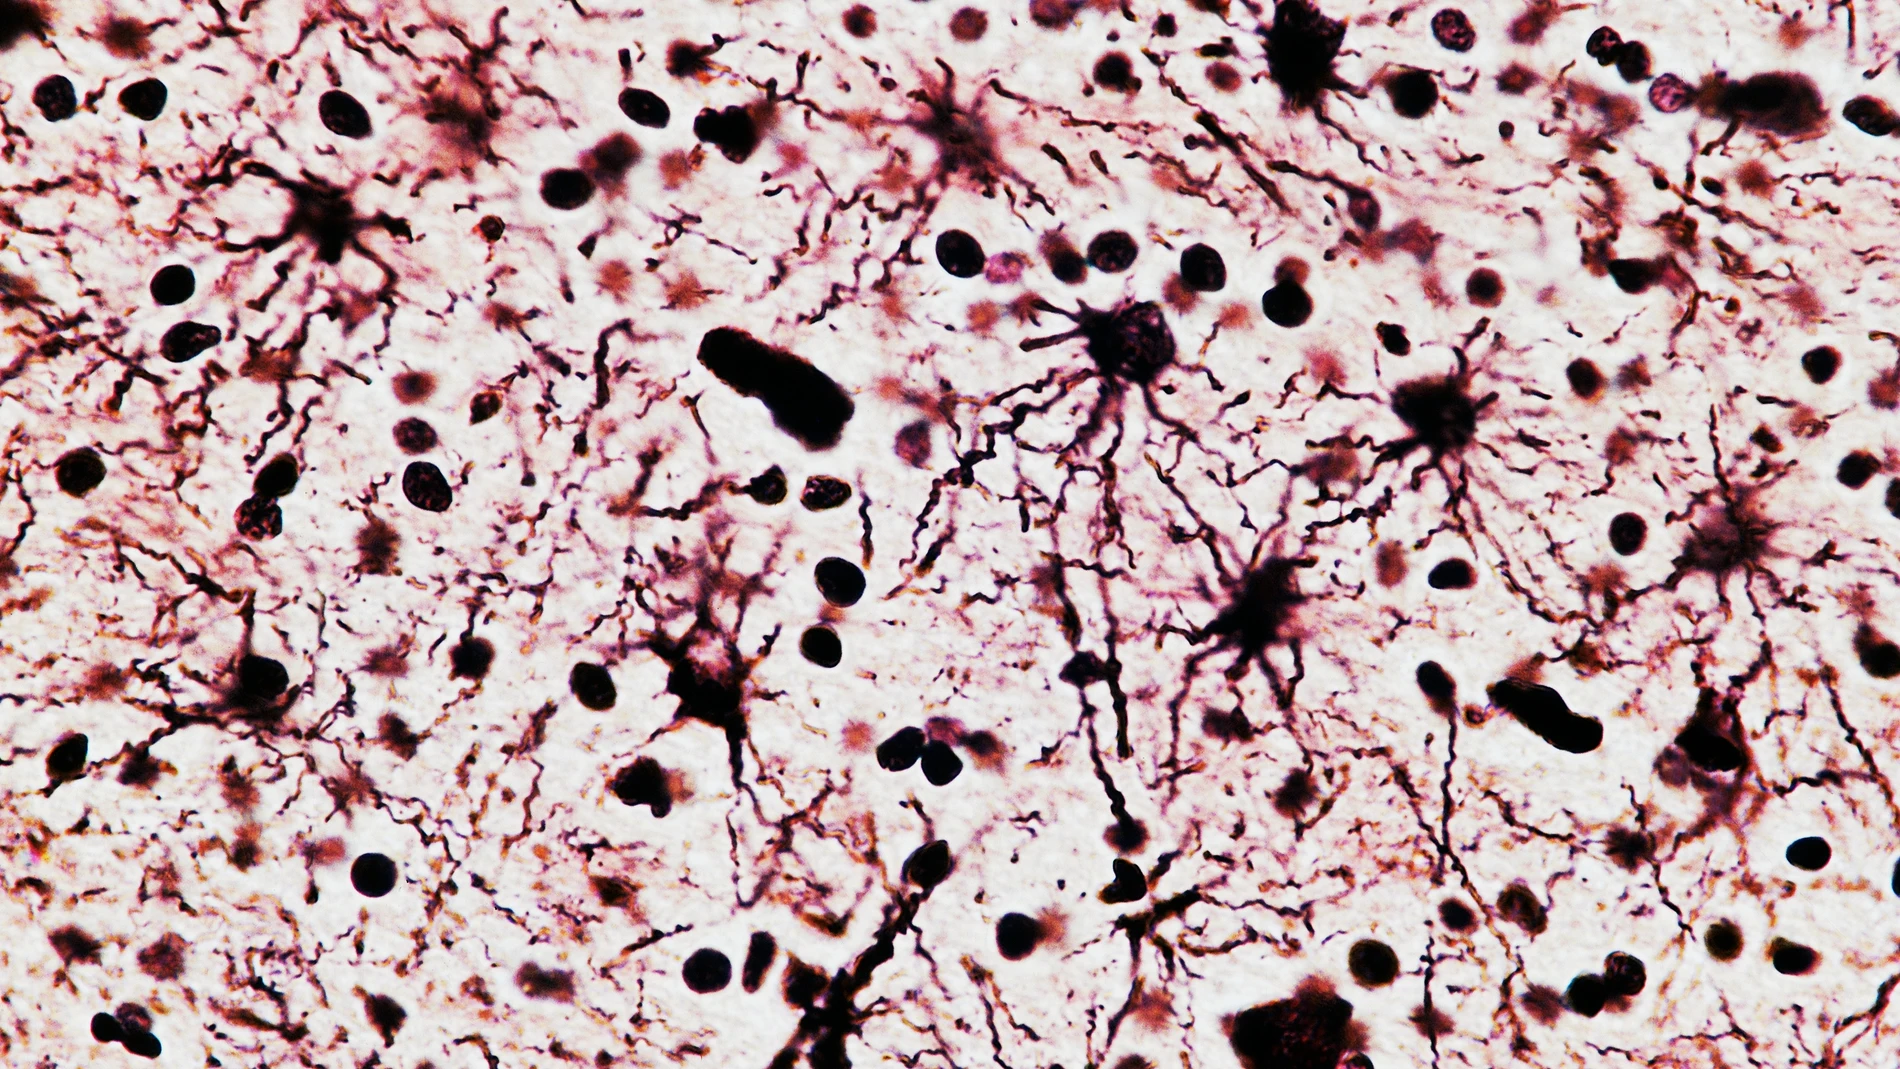

Mediante técnicas avanzadas de registro neuronal, el equipo detectó que la mayoría de las neuronas en la corteza frontal medial se activaban en función de la distancia o progreso hacia el objetivo, de modo análogo a las "células del lugar" que mapean espacios físicos en el hipocampo.

Estas neuronas no sólo señalaban la posición en la secuencia, sino que podían estirar o comprimir su actividad para ajustarse a variaciones en la longitud o duración de las tareas, evidenciando una representación flexible y abstracta del comportamiento.